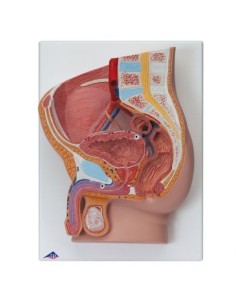

Dal cranio in 22 parti con incastri magnetici ai modelli di colonna vertebrale, da quelli di articolazioni a quelli di cuore, ogni pezzo della nostra collezione è progettato per un’immersione totale nello studio dell’anatomia umana. I nostri modelli, realizzati tramite scansioni di ossa vere, garantiscono un’esperienza tattile autentica e una fedeltà di peso quasi identica agli originali.

Essenziali per studenti e professionisti, i nostri modelli anatomici sono strumenti didattici che permettono di osservare le strutture anatomiche con precisione, eliminando la necessità di dissezioni o studi invasivi. Sono inoltre utili per spiegare ai pazienti le patologie, rendendo la comunicazione più efficace e risparmiando tempo prezioso.